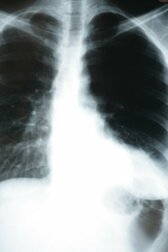

Auswirkungen einer Lungenentzündung auf den Körper

Eine Lungenentzündung oder Pneumonie ist eine akute oder chronische Entzündung der Lungenbläschen. Diese kleinen Bläschen, die auch als Alveolen bezeichnet werden, sind von Blutgefäßen überzogen, in denen der Gasaustausch stattfindet. Das heißt, dass Kohlendioxid (CO2) ausgestoßen und Sauerstoff aufgenommen wird. Die Auswirkungen einer Lungenentzündung auf den Körper können deshalb ernst sein.

Schätzungsweise erkranken jährlich zwischen 2 und 10 von 1.000 Einwohnern an einer Lungenentzündung, wobei 20 bis 35 Prozent davon ins Krankenhaus eingeliefert werden müssen. Die Sterblichkeitsrate beträgt 1 Prozent, kann jedoch bis zu 40 Prozent der ins Krankenhaus eingelieferten Patienten (insbesondere wenn sie sich auf der Intensivstation befinden) ausmachen. Je nach Situation des Patienten kann diese Erkrankung also sehr ernst sein.